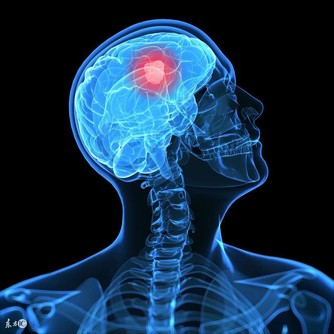

5 、記憶力好:腎精也養大腦。因此腎不好可能會出現經常忘事、反應遲鈍等現象。